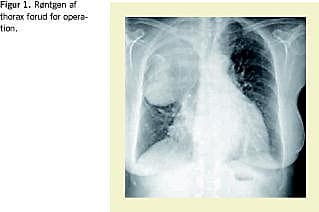

Røntgen viste afrundet fortætning (Figur 1 ) og computertomografi af thorax viste en inhomogen og intratorakal proces, som lå i relation til glandula thyroidea og strakte sig ned i højre side af mediastinum, forårsagende kompression af trachea (mindste tværsnitsareal: 0,81 cm2 ) og højresidige bronkiesystem, hvilket resulterede i atelektase. Processen var solid, stedvis cystisk og med et forkalket område. Endvidere sås bilateralt pleuraekssudat samt perikardieekssudat på 2 cm, men ingen forstørrede glandler i mediastinum eller kompression af kar. Tc-pertechnetat-thyroideaskintigrafi viste svag optagelse i glandula thyroidea uden optagelse svarende til tumor.